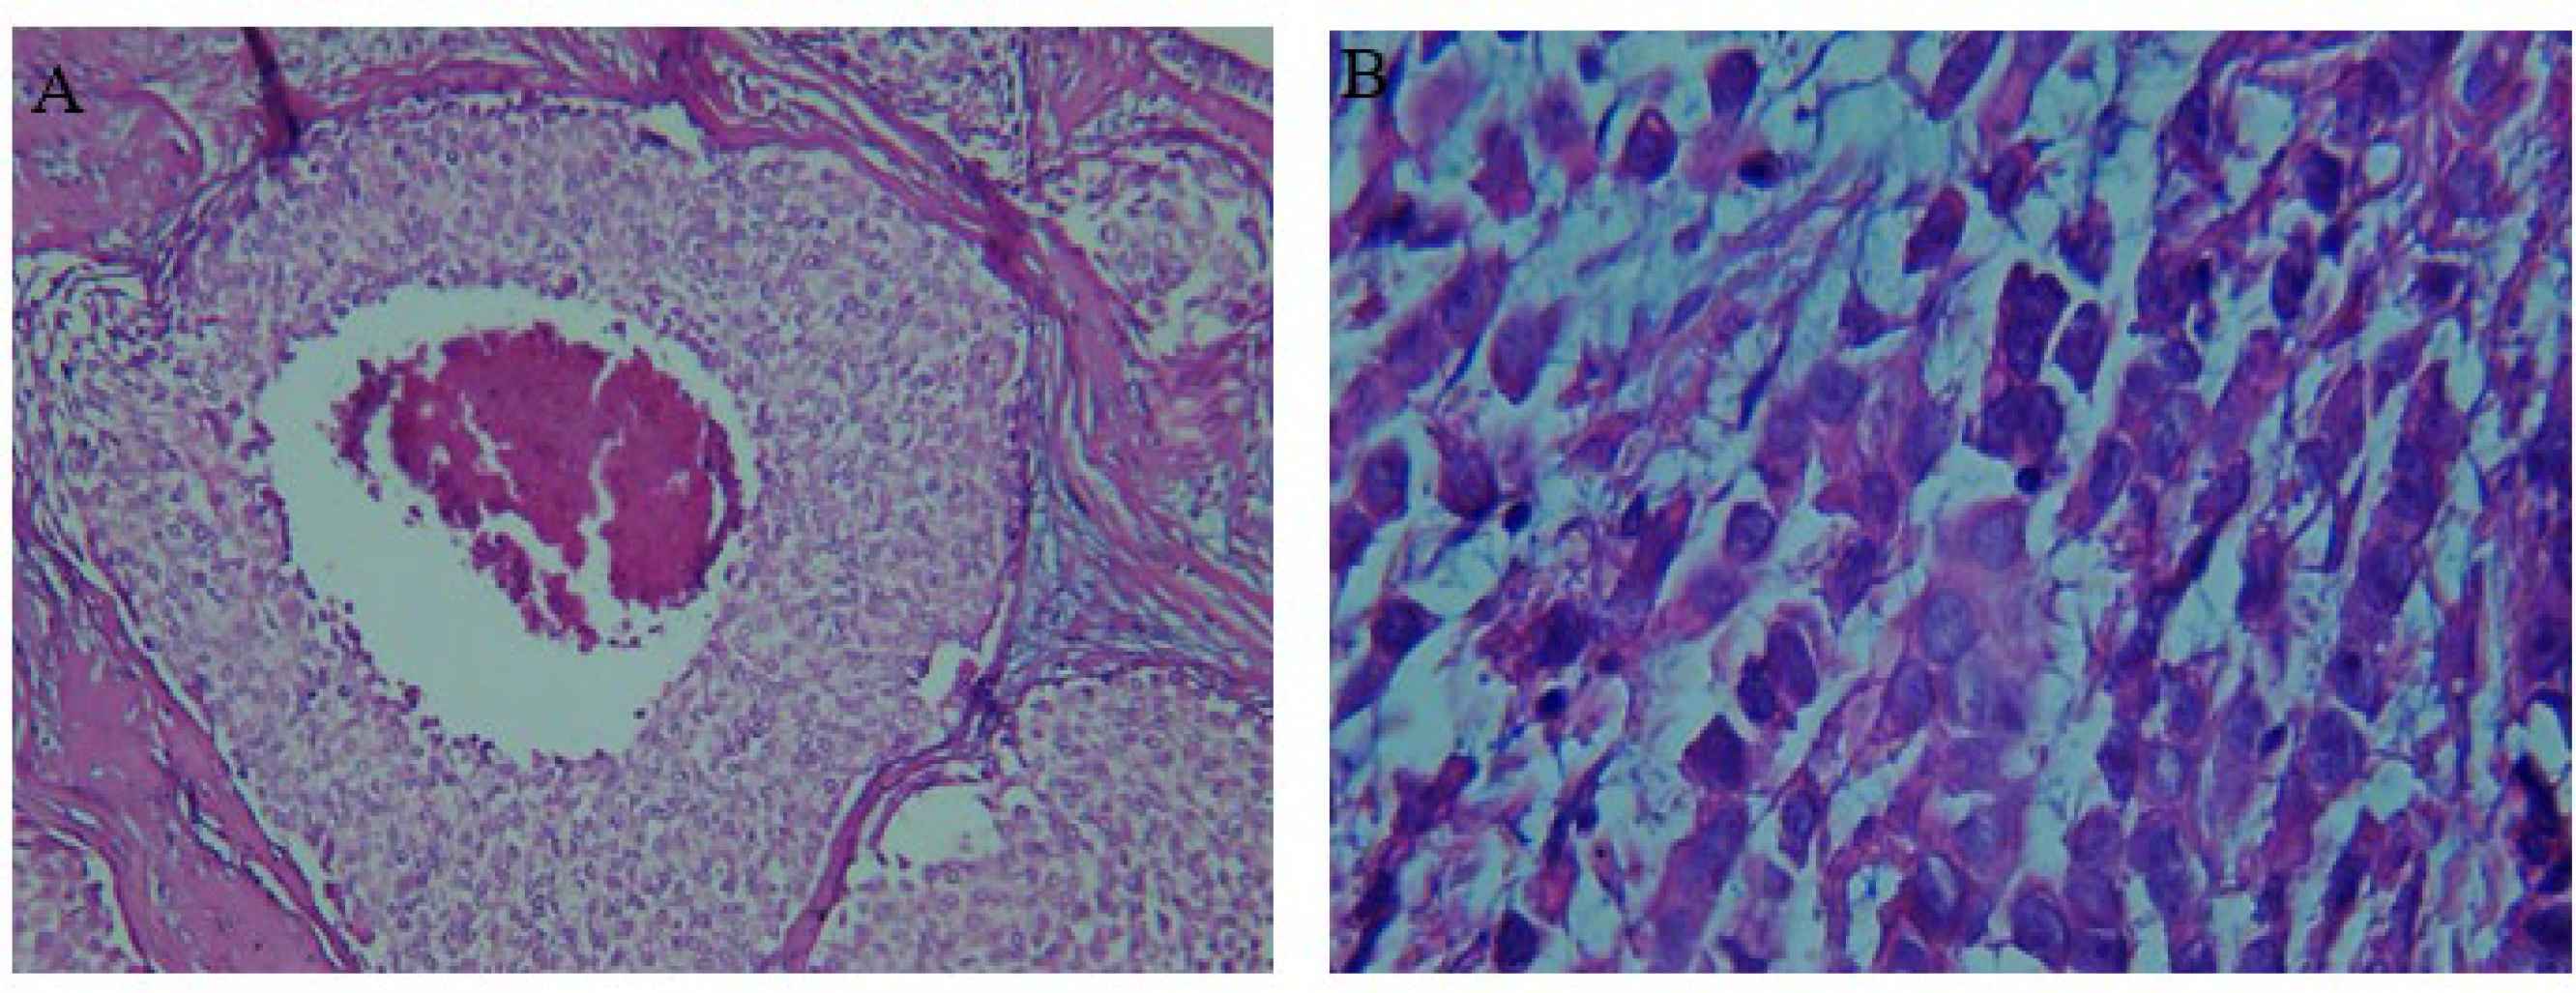

In this study, 102 breast tissue samples were included comprising malignant (cases, n=51) and adjacent non-malignant tissue samples (controls, n=51) obtained from 51 patients. The mean age of volunteers was 50.2±1.4 with a range of 28-68 years. Table 1 presents the patients’ lifestyle parameters, socio-demographic status, and clinical records. In breast cancer patients, 40 had invasive ductal carcinomas (IDC) (78.4%), and 11 had invasive lobular carcinomas (ILC) (21.6%) (Figure 2). Patients’ pathological characteristics are summarized in Table 2.

Fig. 2.Histological sections of hematoxylin-eosin-stained breast tumor tissue. A: invasive ductal carcinoma with tumor grade III and tumor percentage 50%. B: invasive lobular carcinoma with tumor grade I and tumor percentage 50%